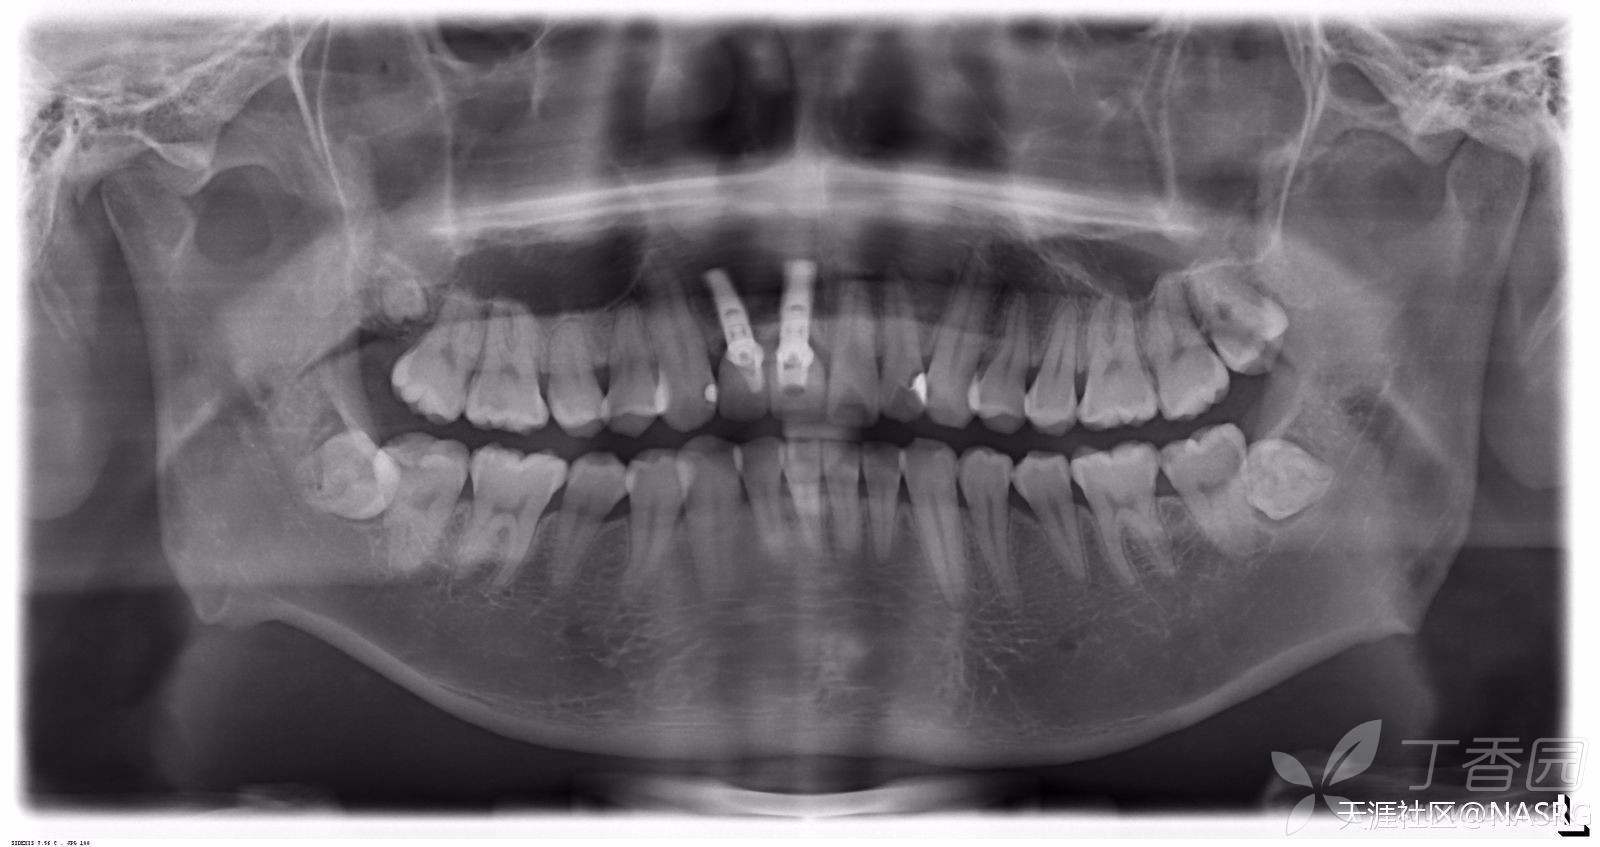

这牙槽骨正常吗

健康的牙槽骨骨质情况图

为什么左边右边骨头明显不对称了?

牙槽骨的吸收程度和类型